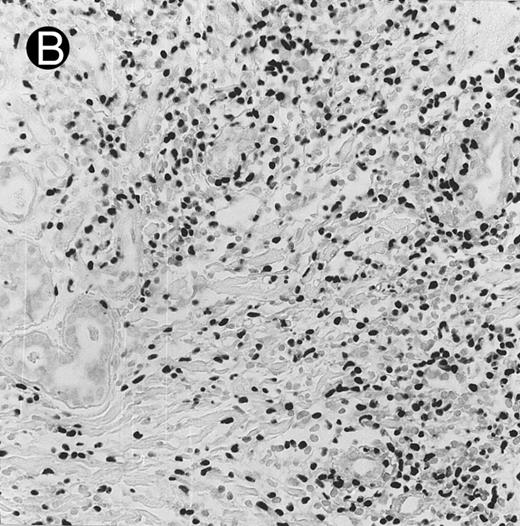

Histologically, the lymphomatous infiltrate was diffuse or patchy, with angiocentric and angiodestructive growth being observed in 30 cases (88.2%) (Figs 1 and 2). The cytologic composition was variable from case to case, including predominance of small cells, medium-sized cells, or large cells, or a mixture of these cell types (Fig 2 and 3). The tumor cell nuclei frequently showed irregular foldings and granular chromatin (Fig 2B). The larger cells possessed distinct nucleoli. The cytoplasm was moderate in amount and often pale. Karyorrhexis was usually prominent. Zonal tumor cell death, focal or confluent, was evident in 27 cases. In the 14 cases for which Giemsa-stained touch preparations were available, azurophilic granules could be identified in at least some of the neoplastic cells.

Laryngeal nasal-type NK/T-cell lymphoma relapsing as perforation of the terminal ileum (case no. 33). (A) The small bowel mucosa shows extensive necrosis and ulceration in the right field. There is also transmural lymphomatous infiltration. Note the vascular occlusion by lymphoma (arrow). (B) Higher magnification shows large and medium-sized lymphoma cells with irregular nuclear contours. The chromatin is fairly dense.